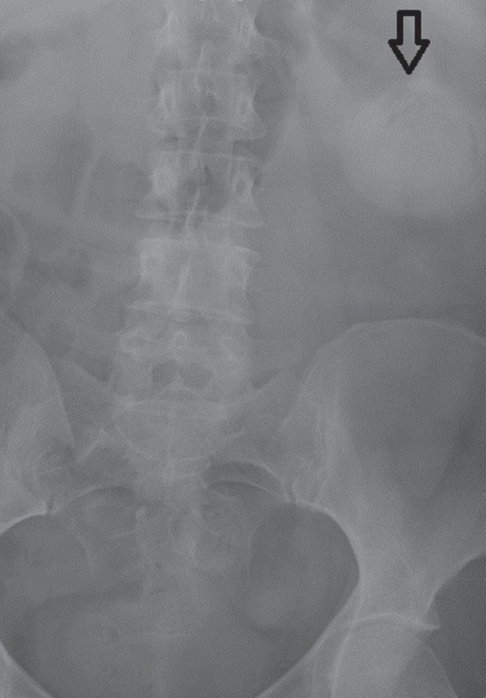

Sophie Lin, MD; Judit Osvath, MD

A 94-year-old woman with a history of moderate dementia and chronic pancreatitis with loose stools was admitted to the inpatient medicine service for 1 day of generalized malaise, low-grade fever, and...